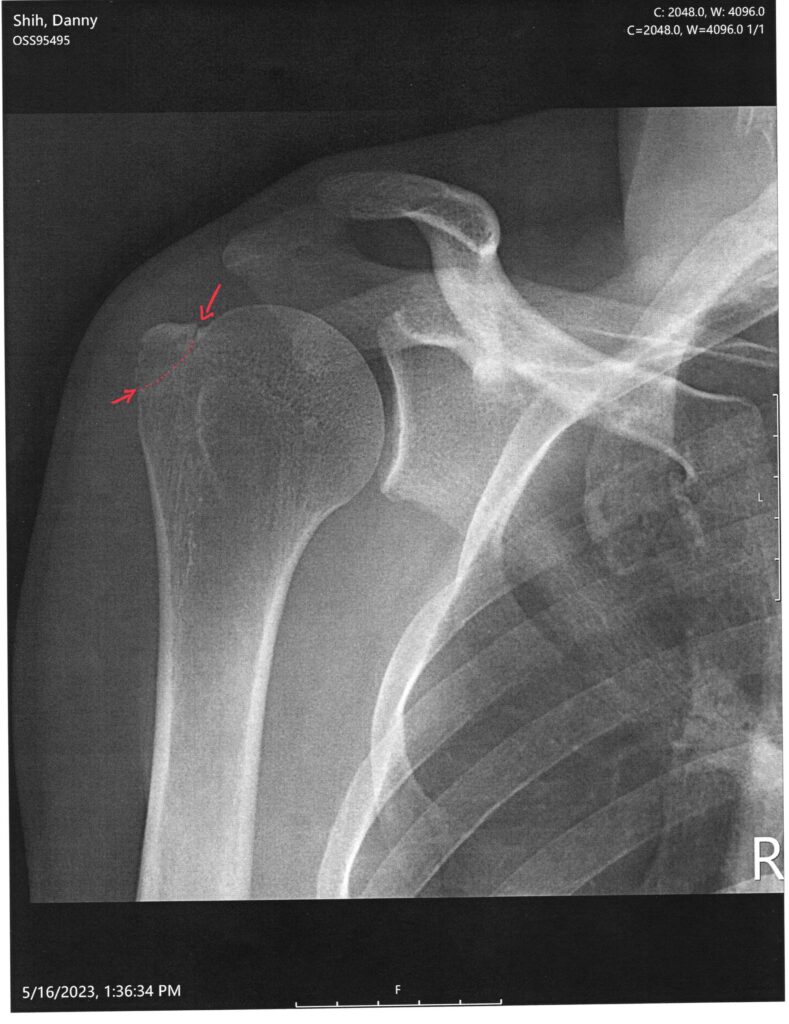

The damage report from the MRI:

- Redemonstrated fracture involving the anterior greater tuberosity.

- Low-grade interstitial tear of the distal supraspinatus tendon at the foot plate insertion.

- Mild subacromial-subdeltoid bursitis.

- Edema within the axillary recess with indistinctness of the joint capsule which is nonspecific and may reflect a capsular tear in the setting of recent trauma versus sequelae of adhesive capsulitis.

- We need to watch it week by week to see if it displaces. It should not, but if it does, we’ll need to operate to align it.